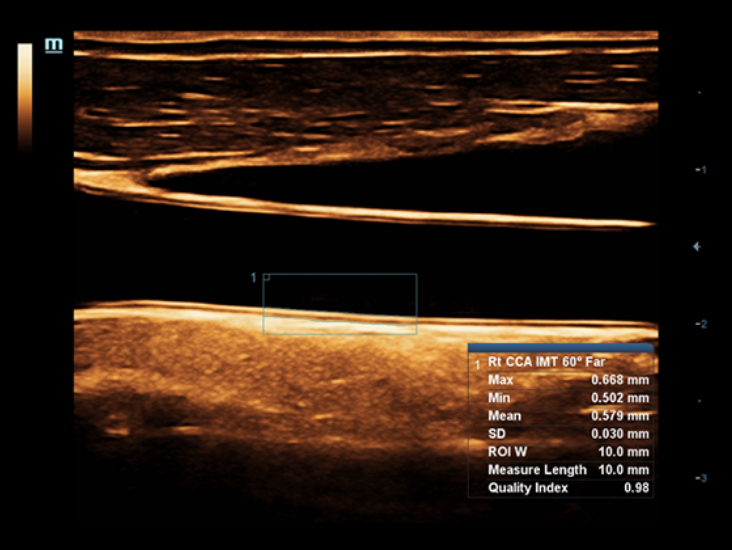

–°–Ņ–Ķ—Ü–ł–į–Ľ–ł–∑–ł—Ä–ĺ–≤–į–Ĺ–Ĺ—č–Ļ —É—Ö–ĺ–ī –Ī–Ľ–į–≥–ĺ–ī–į—Ä—Ź ECHO

–°–ĺ–≤–ľ–Ķ—Ā—ā–Ĺ–ĺ —Ā —Ā–ĺ–≤—Ä–Ķ–ľ–Ķ–Ĺ–Ĺ—č–ľ–ł —É–Ľ—Ć—ā—Ä–į–∑–≤—É–ļ–ĺ–≤—č–ľ–ł —ā–Ķ—Ö–Ĺ–ĺ–Ľ–ĺ–≥–ł—Ź–ľ–ł –Ĺ–ĺ–≤–ĺ–Ķ —Ä–Ķ—ą–Ķ–Ĺ–ł–Ķ –ĺ—ā Mindray –Ņ—Ä–Ķ–ĺ–Ī—Ä–į–∑—É–Ķ—ā –į–ļ—ā—É–į–Ľ—Ć–Ĺ—č–Ķ –∑–į–ī–į—á–ł –ļ–Ľ–ł–Ķ–Ĺ—ā–ĺ–≤ –≤ –ļ–Ľ–ł–Ĺ–ł—á–Ķ—Ā–ļ–ł–Ķ –Ņ–ĺ—ā—Ä–Ķ–Ī–Ĺ–ĺ—Ā—ā–ł. –ü–ĺ—Ā—ā–ĺ—Ź–Ĺ–Ĺ–ĺ —Ä–į–∑–≤–ł–≤–į—Ź—Ā—Ć, —ć—ā–į —Ā–ł—Ā—ā–Ķ–ľ–į —Ā–ĺ—á–Ķ—ā–į–Ķ—ā –≤ —Ā–Ķ–Ī–Ķ —Ā—ā—Ä–Ķ–ľ–Ľ–Ķ–Ĺ–ł–Ķ –ļ –Ĺ–Ķ–ĺ–≥—Ä–į–Ĺ–ł—á–Ķ–Ĺ–Ĺ—č–ľ –≤–ĺ–∑–ľ–ĺ–∂–Ĺ–ĺ—Ā—ā—Ź–ľ –ł –∂–Ķ–Ľ–į–Ĺ–ł–Ķ –∑–į–≥–Ľ—Ź–Ĺ—É—ā—Ć –≤ –Ī—É–ī—É—Č–Ķ–Ķ.

–ú–Ĺ–ĺ–≥–ĺ—Ą—É–Ĺ–ļ—Ü–ł–ĺ–Ĺ–į–Ľ—Ć–Ĺ–į—Ź —Ā–ł—Ā—ā–Ķ–ľ–į DC-60 Exp —Ā X-Insight –Ņ—Ä–Ķ–ī—Ā—ā–į–≤–Ľ—Ź–Ķ—ā —Ā–ĺ–Ī–ĺ–Ļ –ļ–ĺ–ľ–Ņ–Ľ–Ķ–ļ—Ā–Ĺ–ĺ–Ķ —Ä–Ķ—ą–Ķ–Ĺ–ł–Ķ, –ļ–ĺ—ā–ĺ—Ä–ĺ–Ķ –Ņ–ĺ–ľ–ĺ–≥–į–Ķ—ā —É–Ņ—Ä–į–≤–Ľ—Ź—ā—Ć –Ņ–ĺ–≤—Ā–Ķ–ī–Ĺ–Ķ–≤–Ĺ–ĺ–Ļ –ļ–Ľ–ł–Ĺ–ł—á–Ķ—Ā–ļ–ĺ–Ļ –Ņ—Ä–į–ļ—ā–ł–ļ–ĺ–Ļ —Ā –Ľ–Ķ–≥–ļ–ĺ—Ā—ā—Ć—é –ł —É–≤–Ķ—Ä–Ķ–Ĺ–Ĺ–ĺ—Ā—ā—Ć—é.

–ě—Ā–Ĺ–ĺ–≤—č–≤–į—Ź—Ā—Ć –Ĺ–į –≥–Ľ—É–Ī–ĺ–ļ–ĺ–ľ –Ņ–ĺ–Ĺ–ł–ľ–į–Ĺ–ł–ł –Ņ–ĺ—ā—Ä–Ķ–Ī–Ĺ–ĺ—Ā—ā–Ķ–Ļ –ļ–Ľ–ł–Ķ–Ĺ—ā–ĺ–≤, –ļ–ĺ–ľ–Ņ–į–Ĺ–ł—Ź Mindray —Ä–į–∑—Ä–į–Ī–ĺ—ā–į–Ľ–į —Ā–ł—Ā—ā–Ķ–ľ—É DC-60 Exp —Ā X-Insight, —á—ā–ĺ–Ī—č –ĺ–Ī–Ķ—Ā–Ņ–Ķ—á–ł—ā—Ć –≤—č—Ā–ĺ–ļ—É—é –Ņ—Ä–ĺ–ł–∑–≤–ĺ–ī–ł—ā–Ķ–Ľ—Ć–Ĺ–ĺ—Ā—ā—Ć –ł —ā–ĺ—á–Ĺ–ĺ—Ā—ā—Ć –≤–ł–∑—É–į–Ľ–ł–∑–į—Ü–ł–ł –≤–ļ—É–Ņ–Ķ —Ā –Ĺ–į–≥–Ľ—Ź–ī–Ĺ–ĺ—Ā—ā—Ć—é, –ł—Ā–ļ–Ľ—é—á–ł—ā–Ķ–Ľ—Ć–Ĺ–ĺ–Ļ –ł–Ĺ—ā–Ķ–Ľ–Ľ–Ķ–ļ—ā—É–į–Ľ—Ć–Ĺ–ĺ—Ā—ā—Ć—é –ł –ĺ–≥—Ä–ĺ–ľ–Ĺ—č–ľ –ĺ–Ņ—č—ā–ĺ–ľ.